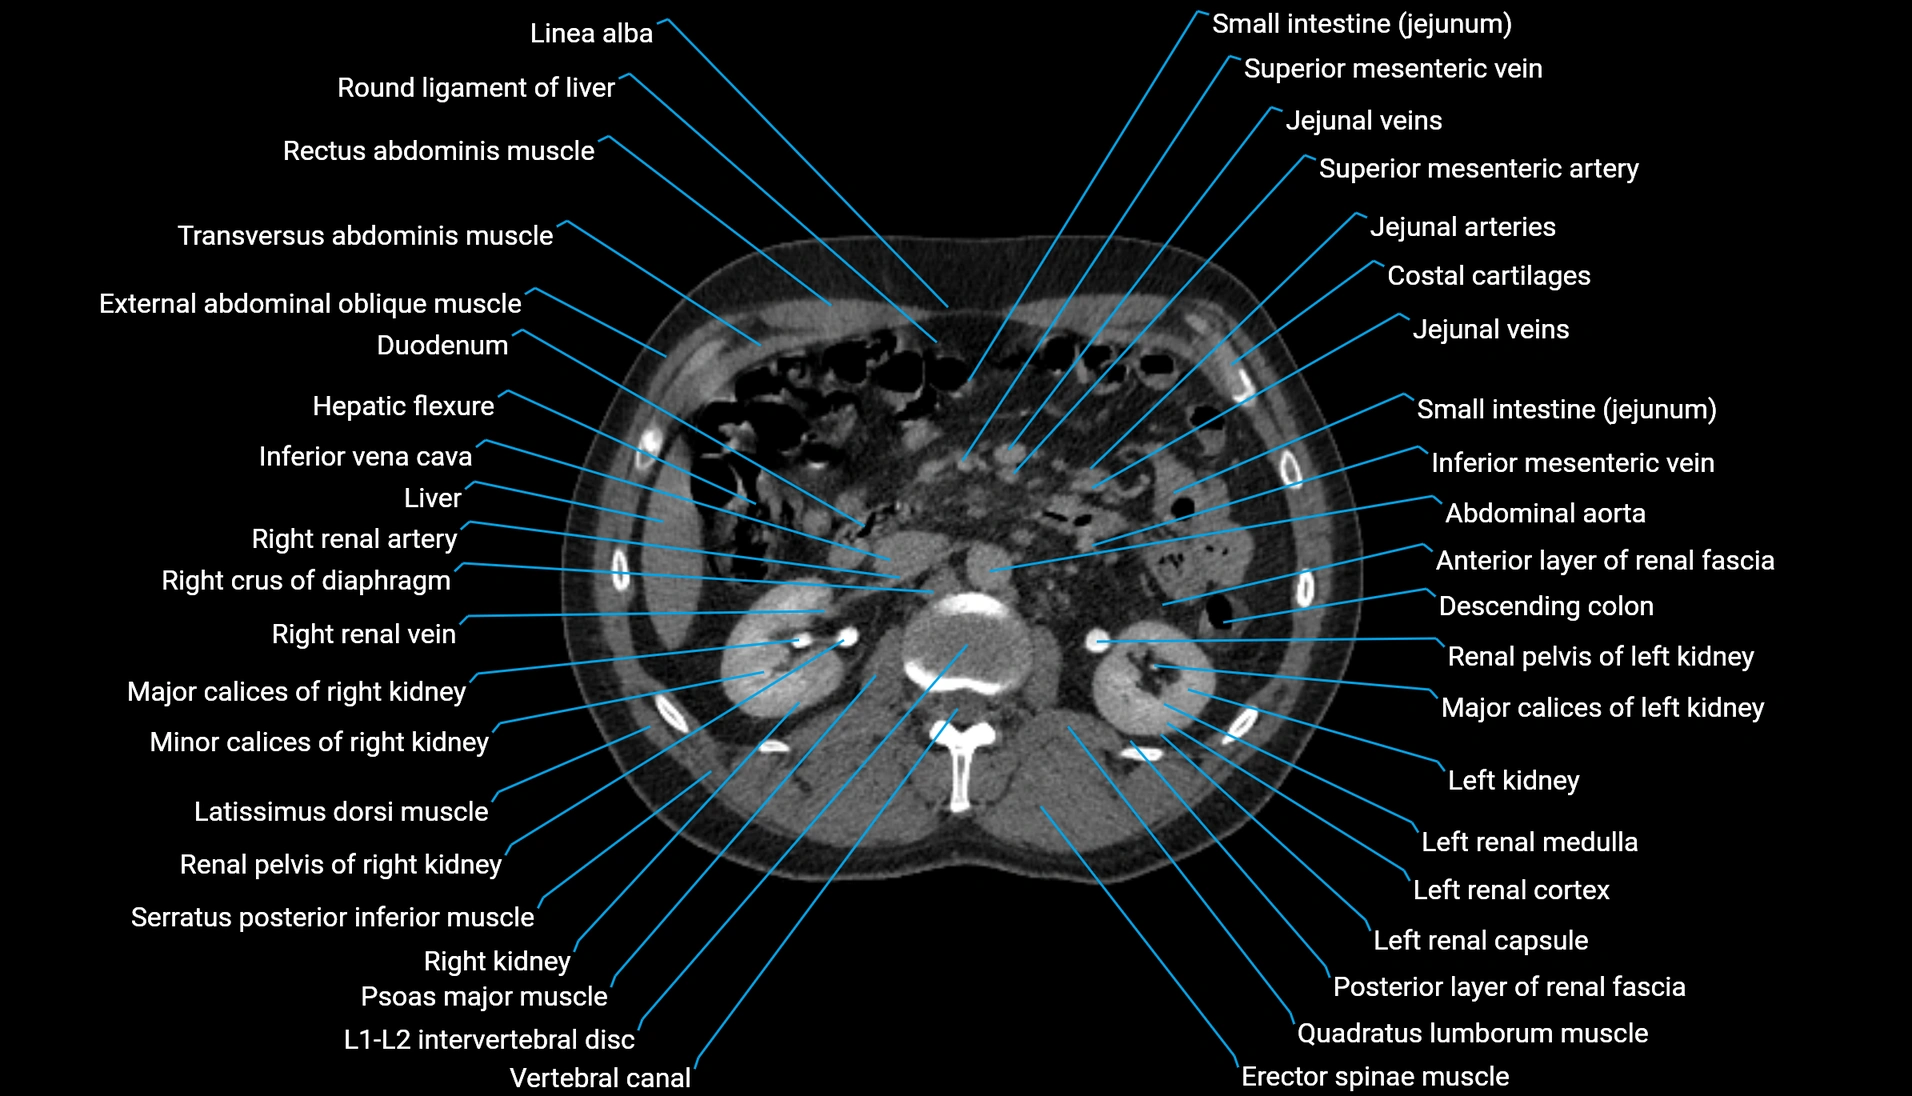

CT Appearance

Non-contrast CT:

-

Demonstrates cortical bone of acetabular rim in excellent detail

Detects fractures, dysplasia, retroversion, or bony overcoverage (pincer impingement)

3D reconstructions used in preoperative hip surgery planning

CT VRT 3D image